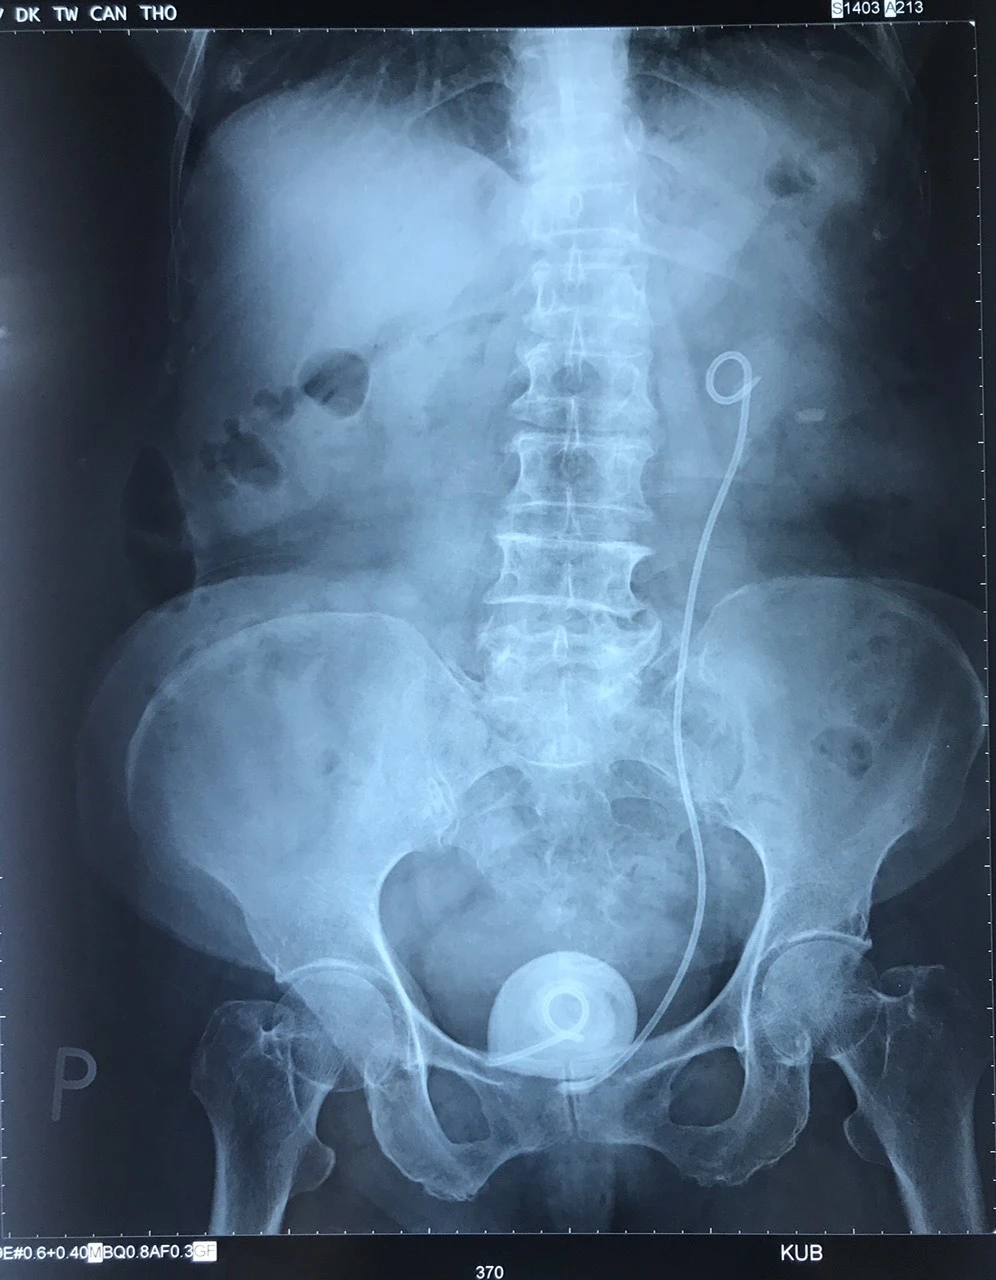

Tại Bệnh viện Đa khoa Trung ương Cần Thơ, sau khi chụp cắt lớp vi tính hệ tiết niệu, các bác sĩ xác định trong cơ thể cụ bà còn ống thông bị đứt đoạn ở vị trí  bàng quang tạo thành sỏi to. Phần đầu trên ống có sỏi nhỏ bám.

Các bác sĩ đã phẫu thuật lấy thành công viên sỏi bàng quang lớn bằng quả trứng, kích thước 5 x 4 x 5 cm có đầu ống thông bên trong, đồng thời rút thành công ống thông.

Viên sỏi bàng quang lớn bằng quả trứng và ống thông trên phim chụp X-quang. Ảnh: Hải Dương